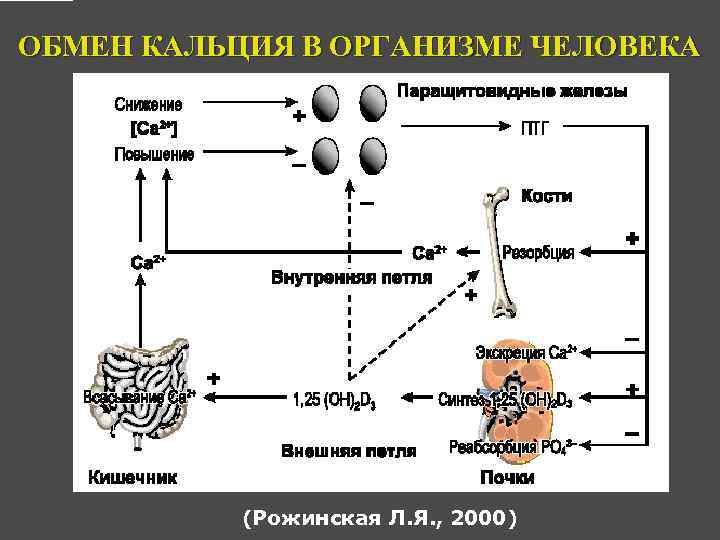

ФИЗИОЛОГИЧЕСКАЯ РОЛЬ ПАРАТГОРМОНА Регуляция обмена кальция и фосфора.

ОБМЕН КАЛЬЦИЯ В ОРГАНИЗМЕ ЧЕЛОВЕКА (Рожинская Л. Я. , 2000)